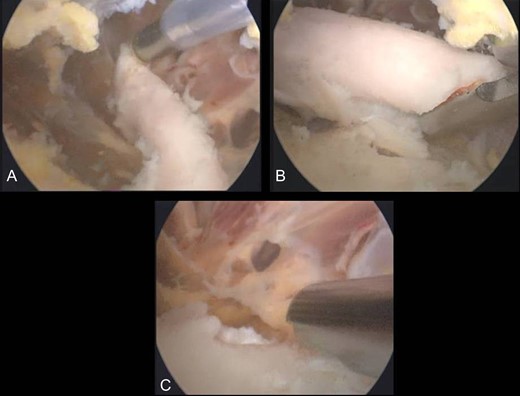

The second case involved an 18 years old male with pain and swelling at the anterior surface of the left knee, under the rectus femoris muscle over the patella. Symptoms exacerbated during knee bending over 90 degrees. X-rays and MRI revealed an extra-articular exostosis, just over the suprapatellar pouch (Figs. 3A and B). Under general anesthesia, a standard antero-lateral portal was used to access the knee arthroscopically. The capsule of the suprapatellar pouch was divided providing access to the adjacent extra-articular osteochondroma. Through a medial, a far supero-medial and supero-lateral portal, the exostosis resected by using an osteotome and removed with a grasper through the supero-lateral portal. The lesion had maximum dimensions 3.1 × 1.4 cm and its histopathological examination set the diagnosis of osteochondroma. Postoperatively, the patient was pain free with full range of knee motion. No recurrence was observed at 9 months (Fig. 4).

(A) X-ray of the exostosis in the second patient, (B) MRI depicts the lesion.